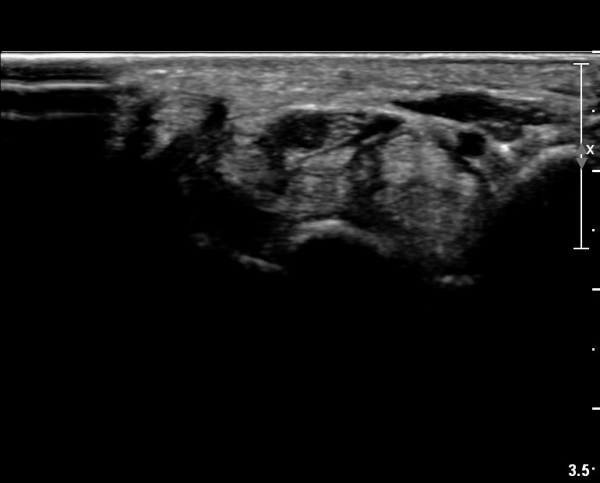

ÃÊÀ½ÆÄ ¼Ò°ß :  ¼Õ¸ñ±ÙÀ§ºÎ Ⱦ´Ü¸é°Ë»ç¿¡¼­ ¼Õ¸ñ±¼±Ù°Ç(FCR)°ú Ç¥Ãþ ¼Õ°¡¶ô ±ÁÈû±Ù(FDS) »çÀÌ¿¡

Á¤Á߽ŰæÀÌ Á¤»óÀûÀÎ ¾ç»óÀ¸·Î º¸ÀÓ(»çÁø 1).

Å½ÃËÀÚ¸¦ ¸»´ÜÀ¸·Î À̵¿ÇÏÀÚ  Á¤Áß½Å굥 ¿äÃø ÀϺΰ¡ Àú¿¡ÄÚ Á¾±«·Î °üÂûµÊ(»çÁø 2).

ÀÌ·± ¸ð½ÀÀº ¼Õ¸ñÀÇ ¿ù»ó°ñ ºÎÀ§(»çÁø 3, 4)¸¦ Áö³ª ¼ö±Ù°ü ±ÙÀ§ºÎ ±îÁö À̾îÁü(»çÁø 5).

Á¤Á߽Űæ Á¾´Ü¸é°Ë»ç¿¡¼­µµ ¼Õ¸ñ ¸»´ÜºÎ¿¡¼­ ¼ö±Ù°ü ±ÙÀ§ºÎ±îÁö À̾îÁø Àú¿¡ÄÚ

Á¾¾çÀÌ °üÂûµÊ(»çÁø 8, 9, 10, 11).